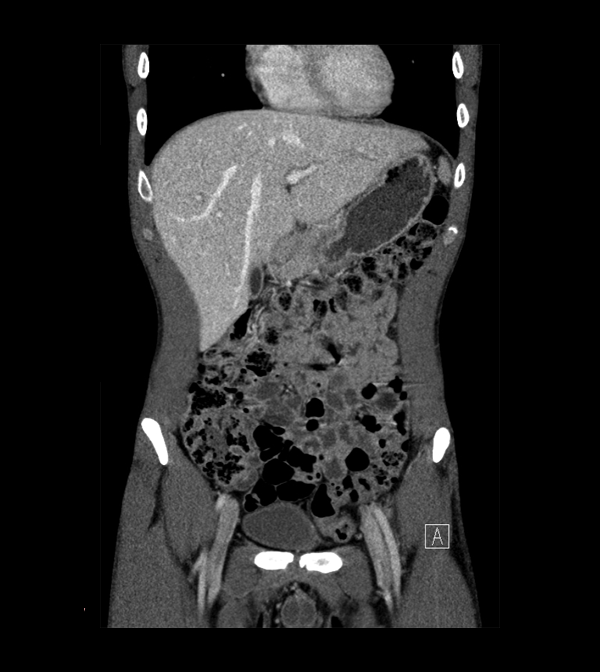

Body

Covers abdominal CT anatomy.